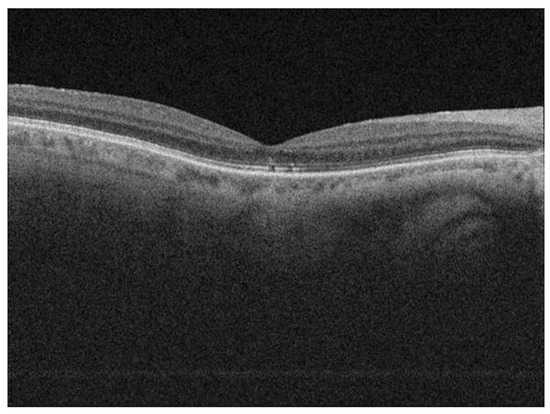

| OCT—discontinuity of ellipsoid zone | |

| No discontinuity | 54 (61%) |

| Discontinuity | 34 (39%) |

| OCT—status of EZ | −0.174 | 0.076 | 0.024 * | −0.325 to −0.024 |